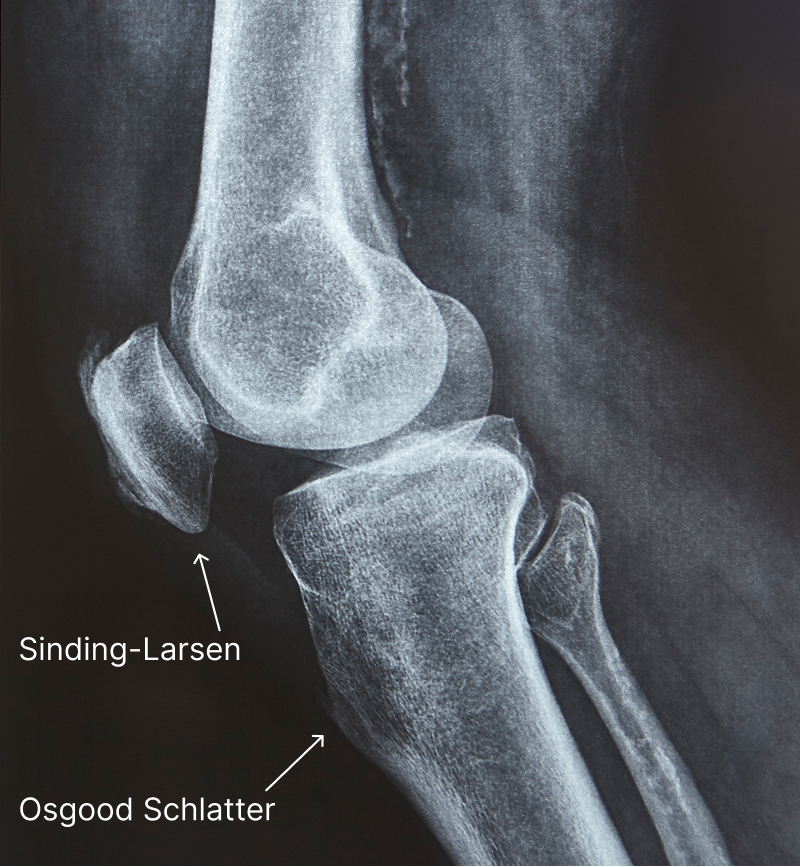

Osgood Schlatter vs Sinding Larsen Johansson: Understanding the Difference

Both conditions involve the patellar tendon—they just affect different ends of it. Think of the patellar tendon as a rope connecting the kneecap to the shin bone. Osgood Schlatter affects where the rope attaches to the shin. Sinding Larsen Johansson affects where it attaches to the kneecap.

The key difference is location. Both conditions cause anterior knee pain that worsens with activity, but they affect different anatomical structures.

The Anatomy:

Imagine the patellar tendon as a bridge:

- The kneecap (patella) is on one end

- The tibial tuberosity (shin bone bump) is on the other end

- The patellar tendon connects them

Both conditions involve this same tendon, but:

- SLJ = problem at the kneecap end of the bridge

- Osgood Schlatter = problem at the shin bone end of the bridge

X-ray Findings:

Osgood Schlatter X-ray may show:

- Fragmentation at the tibial tuberosity

- Soft tissue swelling below the kneecap

- Irregular bone growth at the attachment site

Sinding Larsen Johansson X-ray may show:

- Fragmentation at the inferior pole of the patella

- Calcification at the bottom of the kneecap

- Soft tissue swelling at the patellar origin